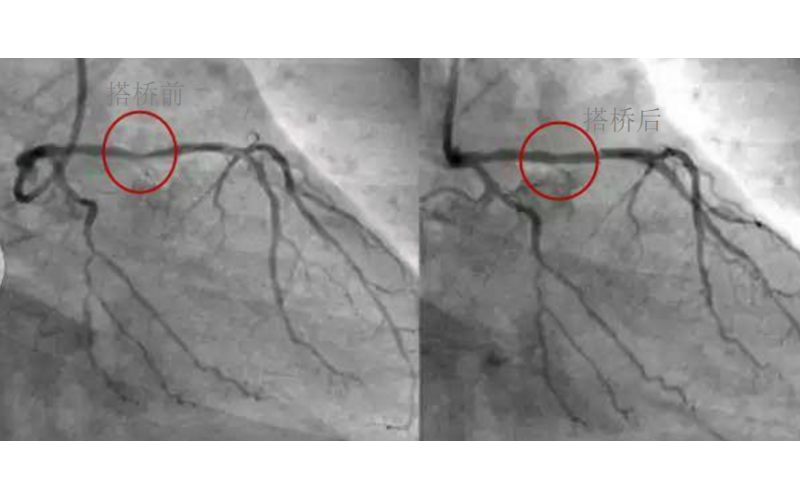

深圳市乐竞网页版入口厂对心脏支架的关注,国产化的道路有多长?